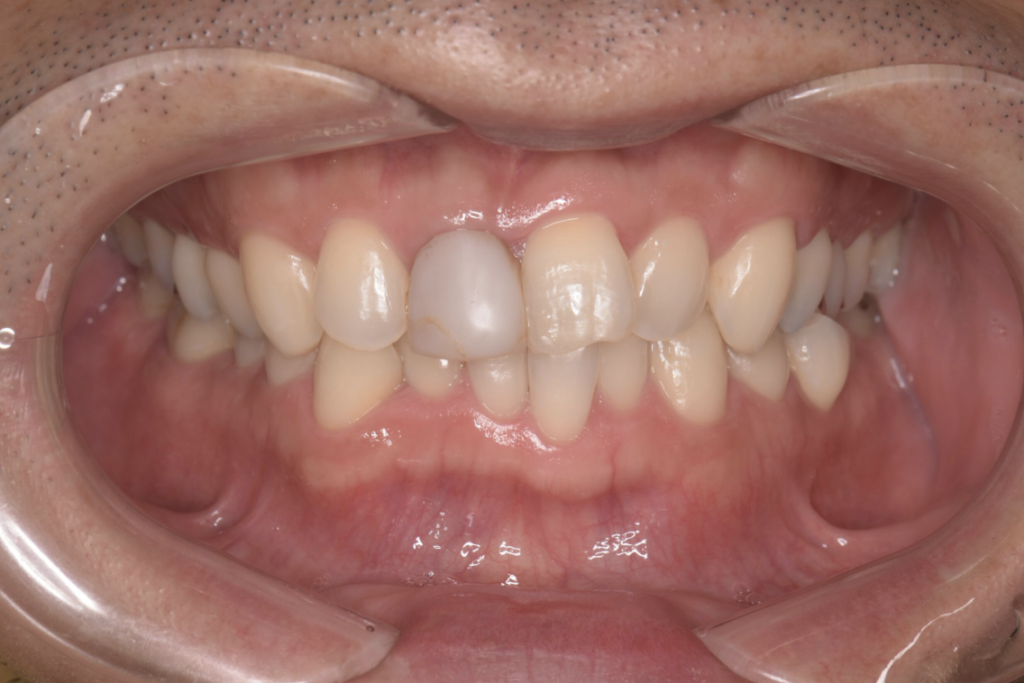

以下の症例写真例は、40代男性の症例です。

前歯のがたつきを改善するためにインビザラインによる矯正とセラミックインレー、根管治療を行い、金属を使わないメタルフリー治療を実施しました。

見た目と機能の両面で大きく改善している様子がわかります。

<術前の症例写真>